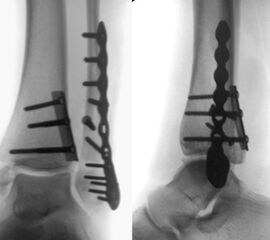

Die Versorgung instabiler Frakturen des medialen Malleolus erfolgt über einen leicht geschwungenen Zugang über den Innenknöchel nach distal verlaufend. Zunächst erfolgt die Exploration des medialen Gelenkanteils und des Frakturspaltes, um eingeschlagenes Periost und Kapselanteile, die eine anatomische Reposition verhindern können, zu entfernen. Anschließend erfolgt die Reposition der Fraktur. Es hat sich bewährt, dies mit einer Spitz-Spitzen-Repositionszange durchzuführen. Dafür erfolgt zunächst eine Bohrung im proximalen Fragment frakturnah um den einen Schenkel der Repositions-Klemme einzuhängen. Der zweite Schenkel wird unterhalb des medialen Malleolus durch das Deltaband eingebracht. Welches Osteosynthese-Verfahren für die Retention der Fraktur gewählt werden sollte, hängt von der Anzahl und Größe der Fragmente, dem Frakturverlauf und der Knochenqualität ab. Bei horizontalem Frakturverlauf und ausreichender Fragmentgröße erfolgt die Fixierung vorzugsweise mittels zweier Zugschrauben (Abbildung 13 & 14). Ist das Fragment zu klein oder handelt es sich um eine mehrfragmentäre Fraktur, so kann die Versorgung wahlweise mit einer Zuggurtungsosteosynthese oder mittels winkelstabiler Hakenplatte erfolgen. Diese Versorgungsarten bieten sich auch bei osteoporotischen Frakturen an.